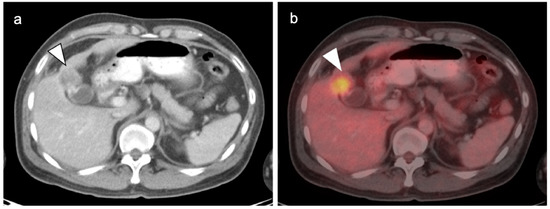

4. Hepatocellular Carcinoma